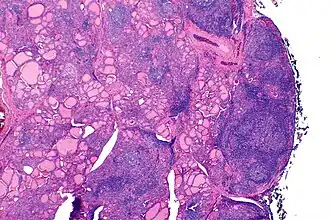

| Tiroide de indivíduo com tiroidite de Hashimoto observada em microscópio de baixa ampliação | |